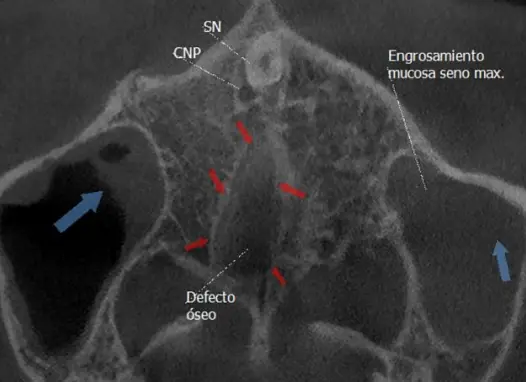

TOMOGRAFÍA DE FISURA PALATINA

Permite evaluar con gran precisión los defectos óseos localizados en el maxilar superior.

TOMOGRAFÍA PARA SENOS PARANASALES

Preciso para diagnosticar sinusitis, pólipos, obstrucciones, fracturas o tumores, ya que muestra huesos, mucosas y secreciones, y ayuda a planificar cirugías